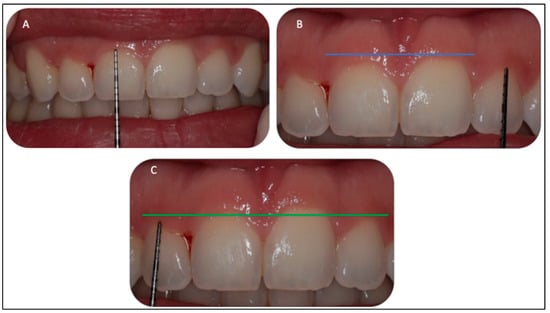

2.5.1. Gingivoplasty Procedure